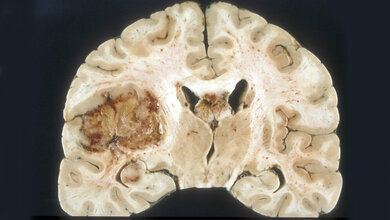

Diffuse Mittellinien-Gliome zählen zu den aggressivsten Hirntumoren. Sie treten meist bei Kindern und jungen Erwachsenen in der Nähe des Hirnstamms auf und sind daher operativ nur schwer zugänglich. Auch Chemo- oder Strahlentherapie sind nur begrenzt wirksam. Bei dieser Krebsart treten charakteristischerweise Mutationen im Gen für das Histon H3 (H3K27M) auf, einem Verpackungsprotein der DNA. Die Mutation lässt eine neuartige Proteinstruktur entstehen – ein so genanntes Neoepitop, das vom Immunsystem des Patienten als fremd erkannt werden kann.

Entscheidend für den Erfolg von Krebsimpfungen sind Proteinstrukturen, an denen die Immunzellen den Krebs erkennen können – und die auf gesunden Zellen nicht (oder nur in geringem Maße) vorhanden sind. Mutationen im Tumorerbgut führen häufig zu krebstypisch veränderten Proteinstrukturen. Die Forscher um Katharina Sahm und Michael Platten bauten den Abschnitt des Histon H3-Proteins mit der charakteristischen Mutation synthetisch nach. Mit diesem Peptid konnten sie an einem Maus-Modell das Wachstum von H3K27M-mutierten Tumoren drosseln*. Ermutigt von den Ergebnissen entschied das Team, den an der Universität Tübingen hergestellten mutationsspezifischen Impfstoff in einer Phase1-Studie (INTERCEPT-H3), die noch nicht abgeschlossen ist, bei Patienten zu prüfen.